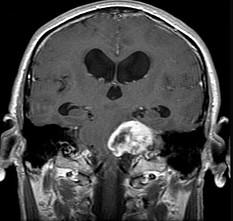

问题 有关听神经鞘瘤(如图所示)的发生,下列哪项描述不正确()

选项 A.多发生于听神经的内听道段或内耳孔区 B.听神经瘤起源于Schwann细胞 C.听神经瘤多来自耳蜗神经 D.大多数是单侧性 E.好发于中年人

答案 C